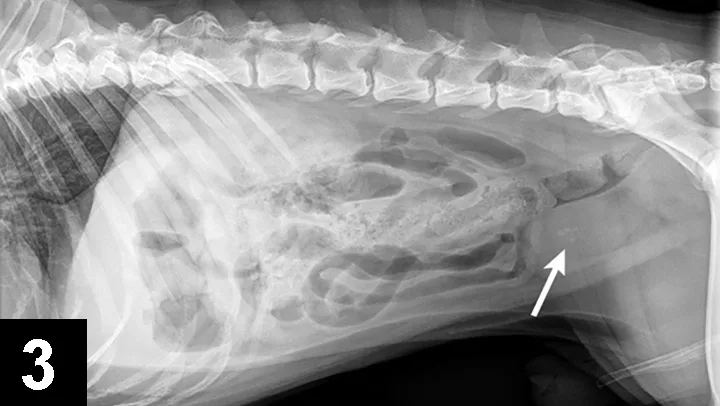

Cystine crystals are flat, colorless, and hexagonal. The sides of the hexagon may or may not be of equal lengths, and the crystals tend to aggregate in urine sediment, resulting in a layered appearance (Figure 2). Cystine uroliths have intermediate radiodensity; they are typically less radiodense than calcium oxalate and struvite uroliths but more so than ammonium urate uroliths (Figures 3 and 4). In some cases, contrast urethrocystography or ultrasonography may be necessary to visualize uroliths. Cystine uroliths are usually smooth and spherical and range in size from less than 1 mm to greater than 3 cm in diameter. Affected dogs frequently present with multiple cystine uroliths (Figure 5). Secondary urinary tract infections are uncommon.

FIGURE 4 Tucked lateral radiograph of the dog from Figure 2 showing additional calcium oxalate urethroliths (arrow).